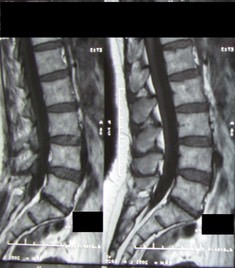

At the end of the treatment, the patient was asymptomatic, and a new MRI was ordered.

The new MRI was NORMAL. The previously reported large L4-5 disc was completely resorbed. (see picture below)